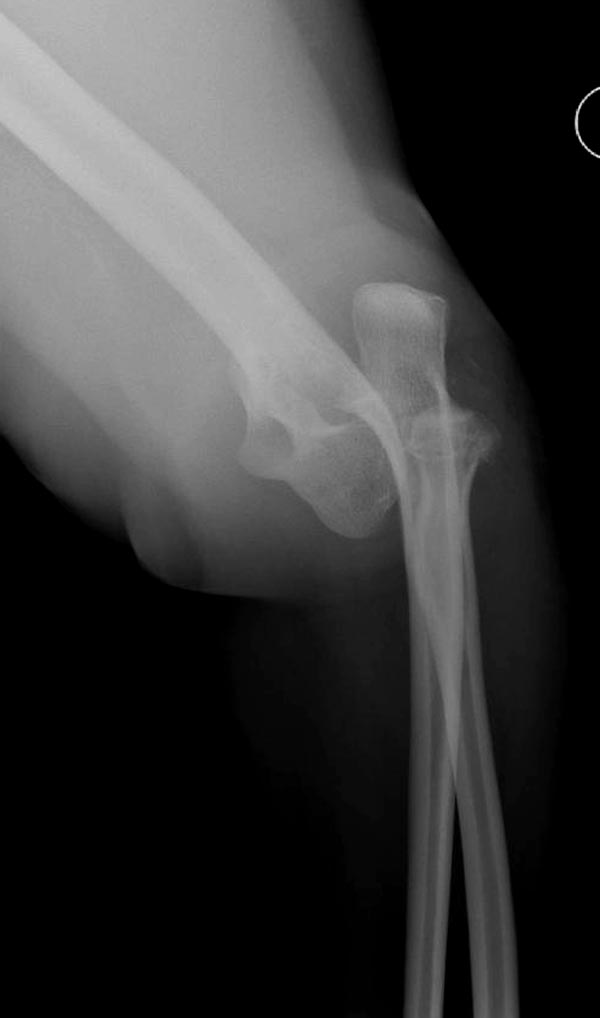

Re: ПЕРЕЛОМ ГОЛОВКИ ЛУЧЕВОЙ КОСТИ.

Второе наблюдение